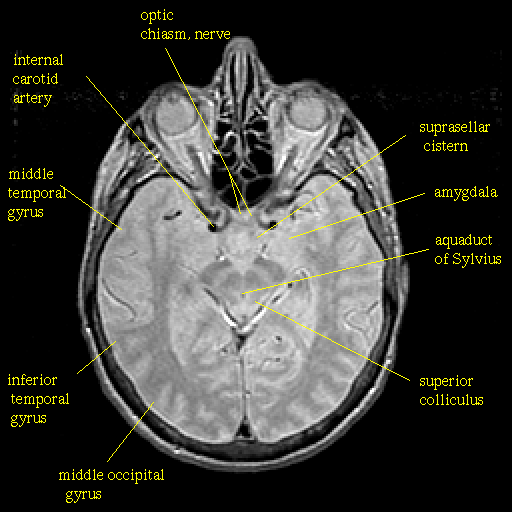

Proton density-weighted structural MR: Slice 23

Slice 23